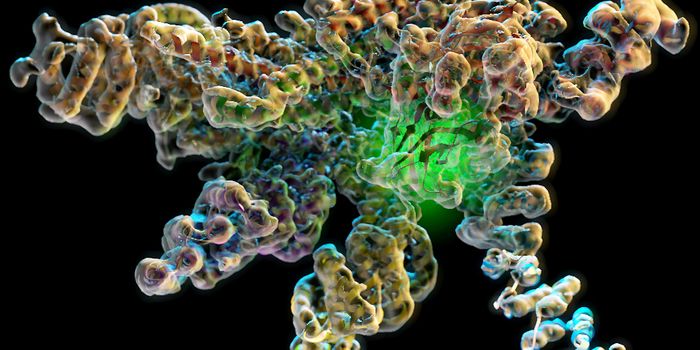

JAN 26, 2016CancerTSRI and UC Berkeley Team Solves Structure of 'Flipping' Cellular Machine, Pointing to Possible Alzheimer’ ...